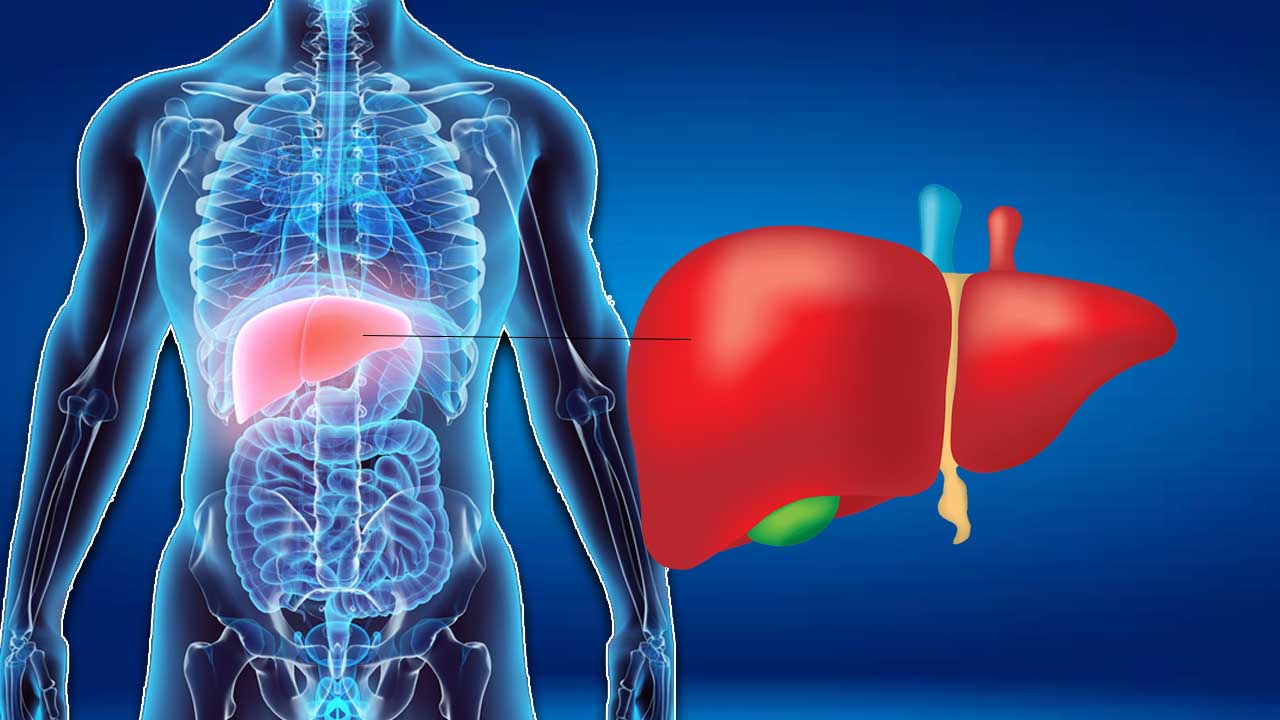

Noodles effect on Health | నూడుల్స్ తింటున్నారా.. అసలు నిజాన్ని తెలుసుకోండి..